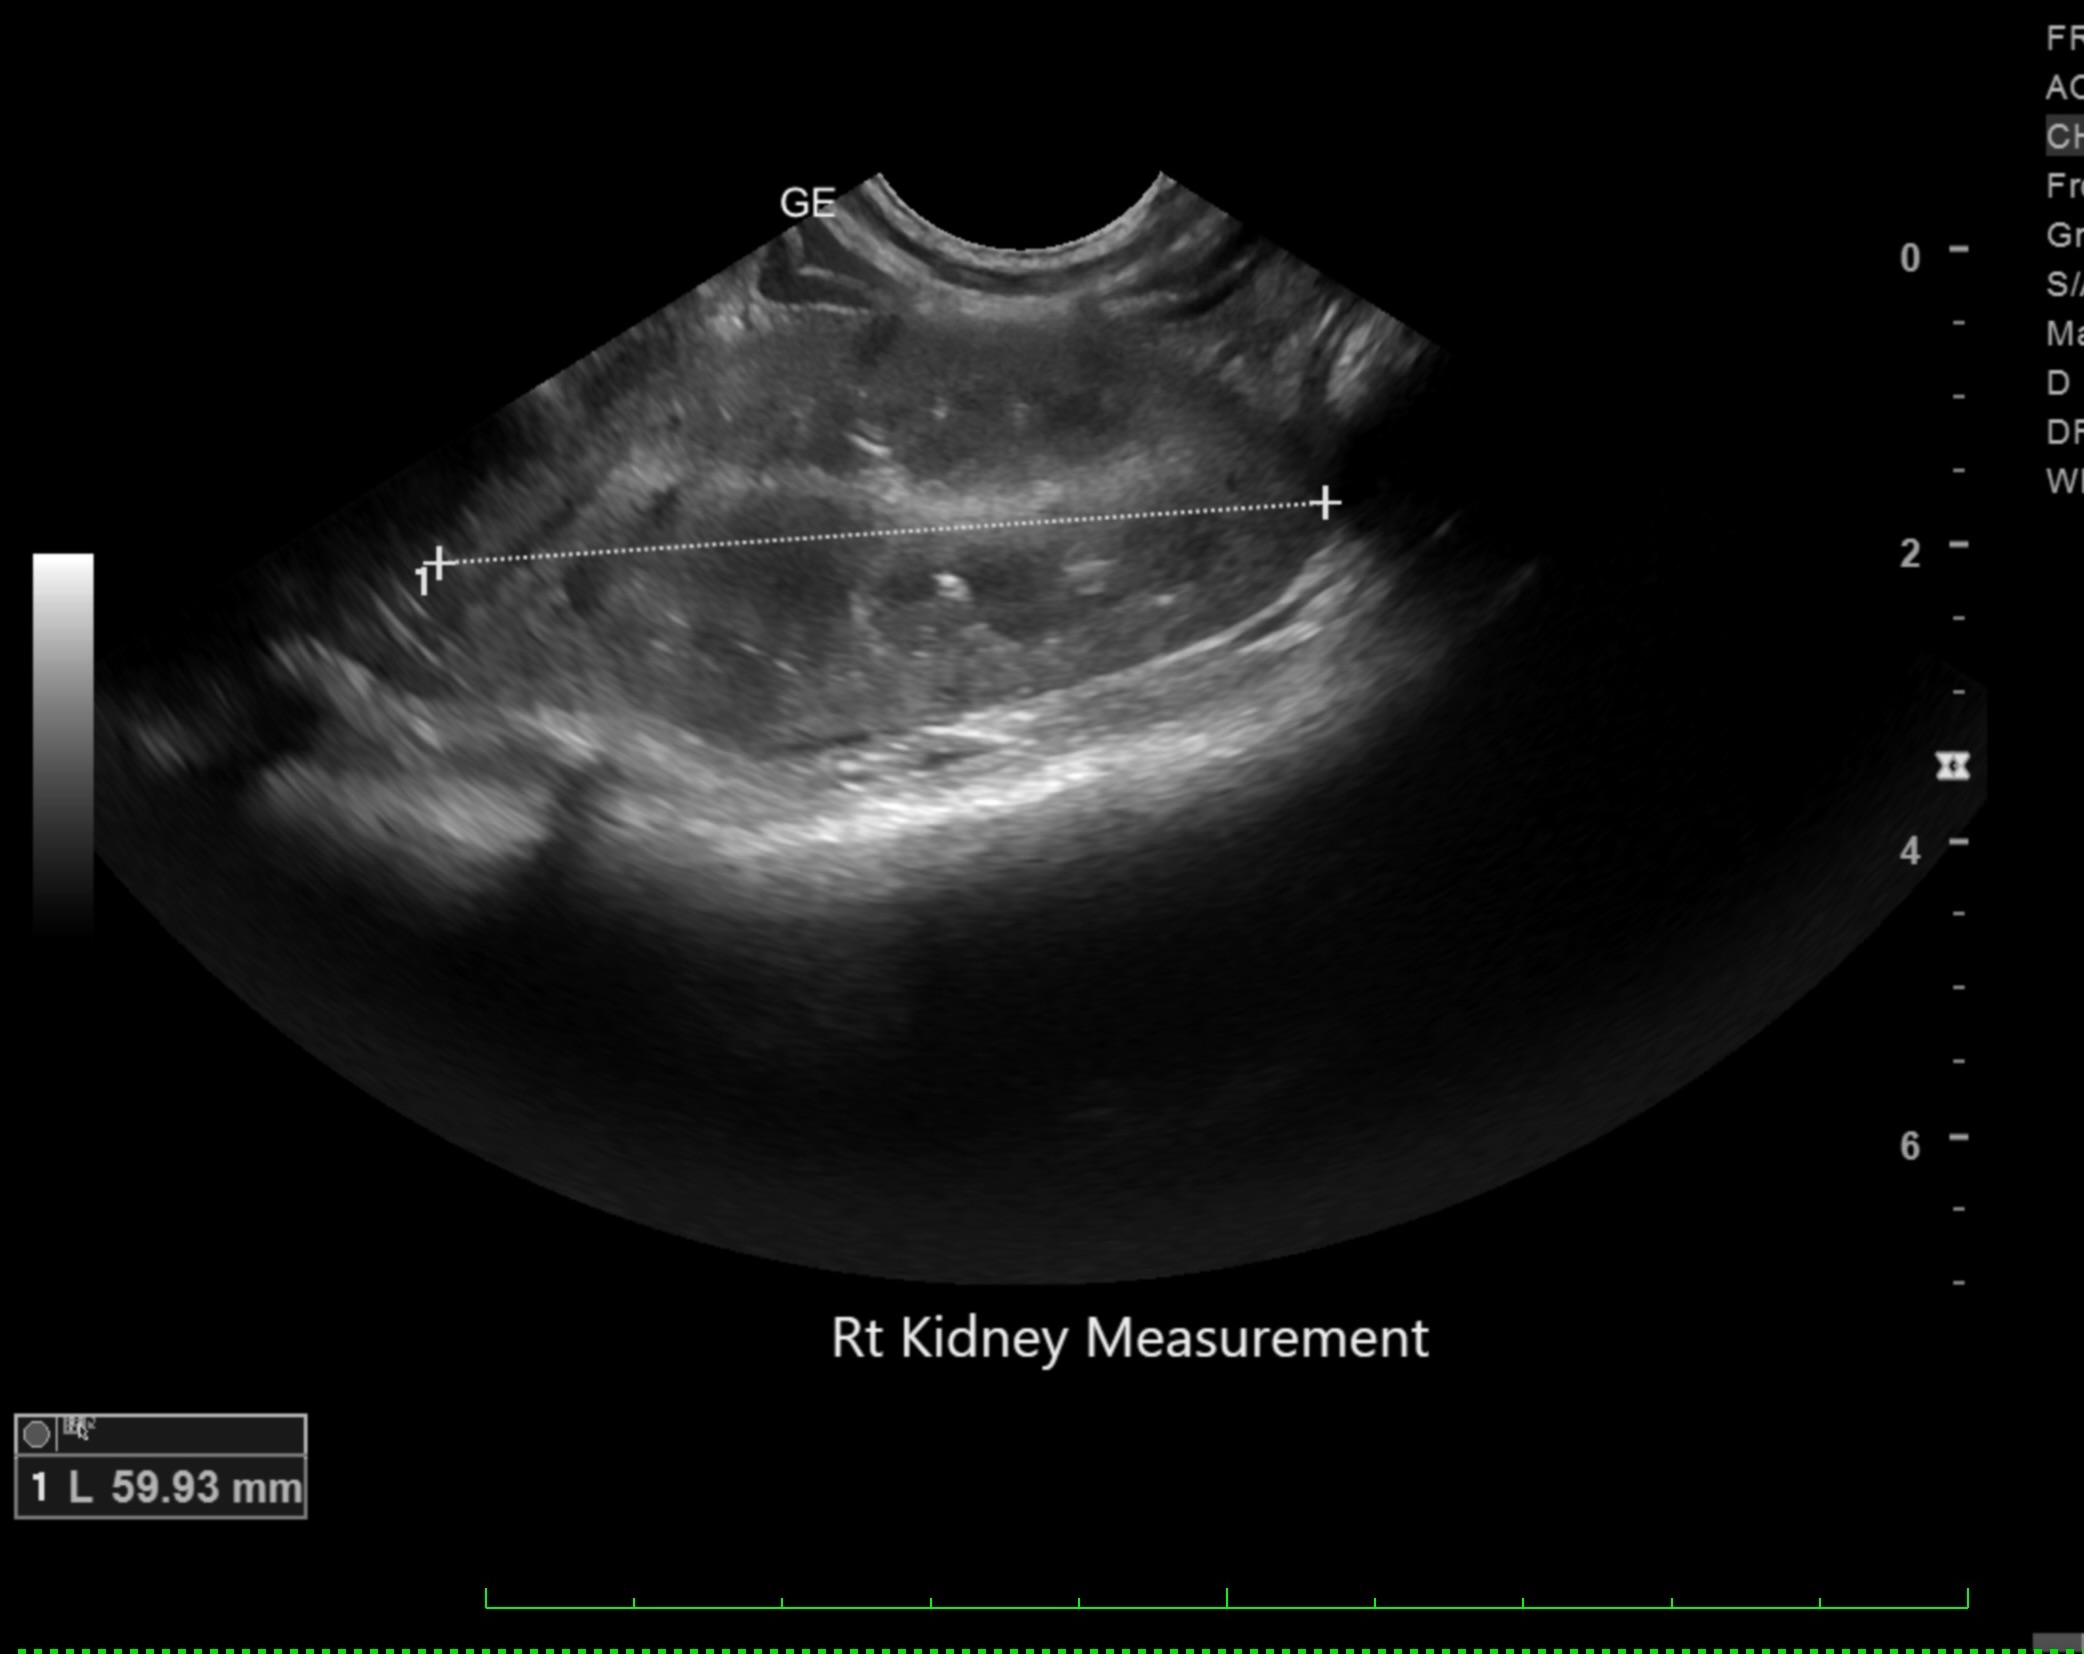

Labwork (fasted): TP 4.5, Alb 2.5, ALP 144, ALT 155, GGT 3, Bili 0.4, Cre 0.3, Cho 51, Amy 266 CBC – HCT 39%, Hgb 12.0 UA – USG 1.030pH 6, 1+ bilirubin, WBC 4-10/hpf, rods 26-50/hpf Negative Accuplex Bile Acids: Pre 299.2, Post-meal – 90.7